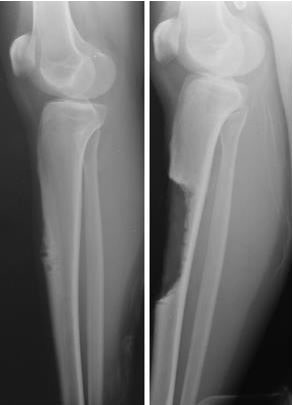

adamantinoma before and after limb salvage

(Left) This x-ray taken from the side shows an adamantinoma in the tibia. (Right) The tumor and surrounding bone have been removed and replaced with an autograft.